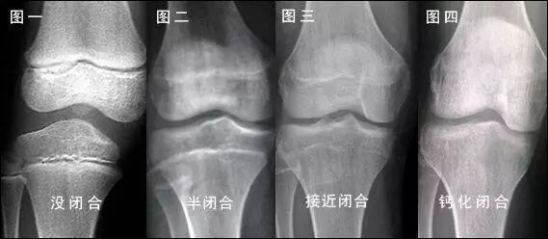

比如一些补品中,性激素含量往往较高,虽然短期内看起来孩子快速长高了,但却会导致孩子的骨骺提前闭合,最后身高反而不如同龄人。宝宝长高的秘诀 想要宝宝长高这2件错误事情要改